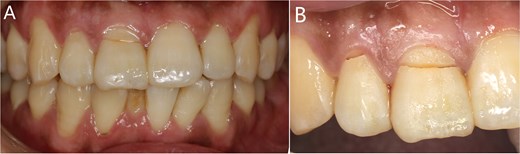

The alveolar crest contour was still stable at 1 year of follow-up, and the patient was satisfied with his final prosthesis, which was in harmony with adjacent teeth (Fig. 6).